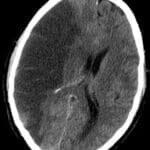

ICH

ICH patient Intubated

ICH patient not intubated